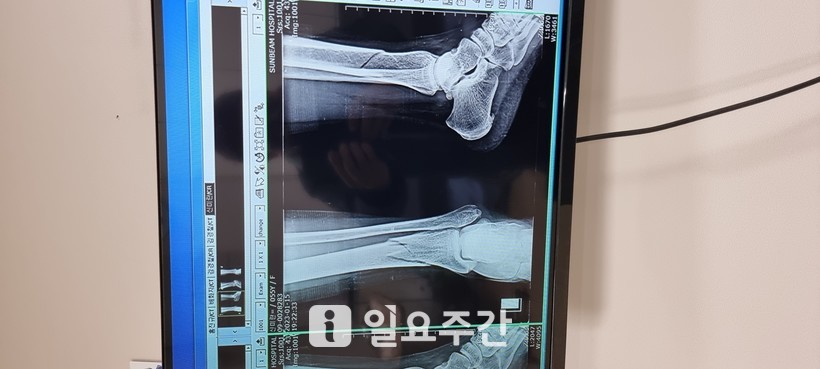

![]() |

▲A 씨는 현재 발목 골절로 철심을 박은 상태다. (사진=제보자 제공) |

진단 결과 발목이 골절돼 전치 8주 진단을 받았다.